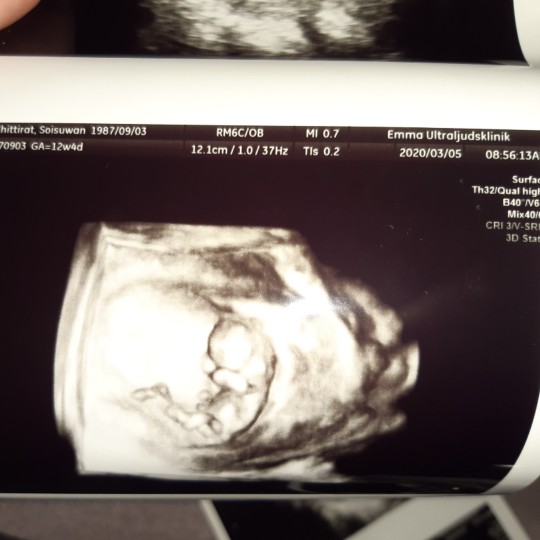

12+4 จ้า